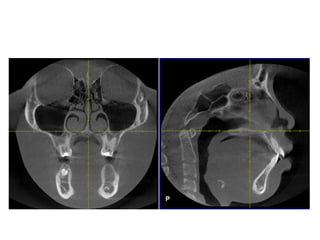

Enlarged adenoids

• Enlarged adenoids correlated with the open

mouth position.(AJR Am J Roentgenol. 2002

Aug;179(2):503-8 )

• The nasopharynx and hypopharynx changes only

minimally with respiration any motion greater

than 5 mm should be considered abnormal.

• Adenoid enlargement most likely does play a role

in the development of obstruction in obstructive

sleep apnea.